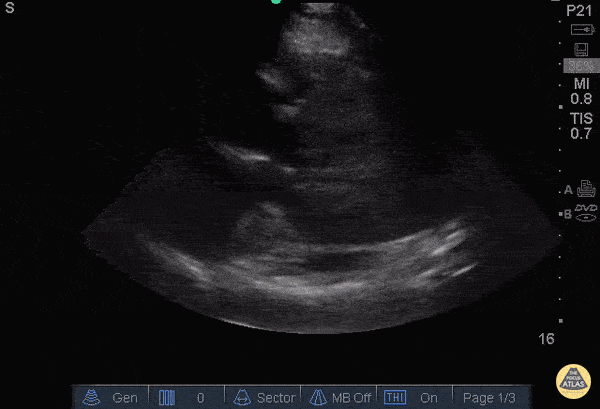

Other Cardiac Pathology - A Fib with Left Atrial Thrombus (parasternal long)

40 y/o M with atrial fibrillation, off his anticoagulation, presented with shortness of breath and was found to have a left atrial thrombus on POCUS in this parasternal long view. Differentiating a thrombus from an atrial myxoma is difficult, but seeing the object tumble and shoot around the atrium, in the setting of afib, is both dramatic and suggestive of a thrombus. Unfortunately, timing does not differentiate the two since the average myxoma can grow at up to 0.5cm/month. The patient was admitted to the cardiac intensive care unit with full resolution of the thrombus after anticoagulation. Dr. Bryan Jarrett and Dr. John Kilpatrick - SUNY Downstate/Kings County Emergency Medicine